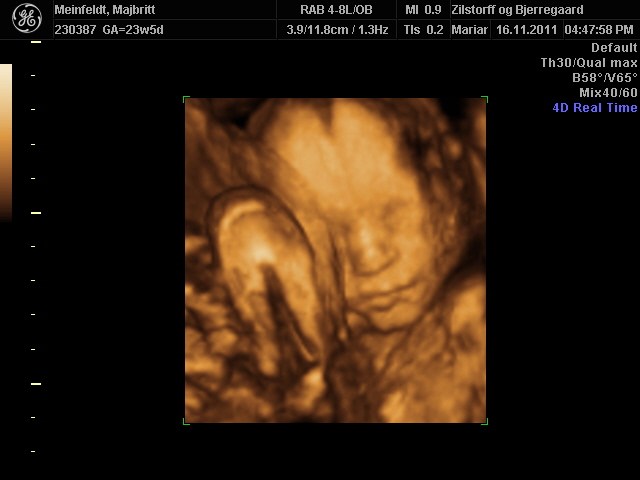

Hvor er det dejligt for jer, at have fået set jeres skønne børn.. Der er bare nogle rigtig fine billeder..

Vi har godt nok valgt ikke at få en 3D skanning, men man bliver helt varm om hjertet når man ser de fine billeder.. Og som der er skrevet længere oppe, der er jo lang tid til marts